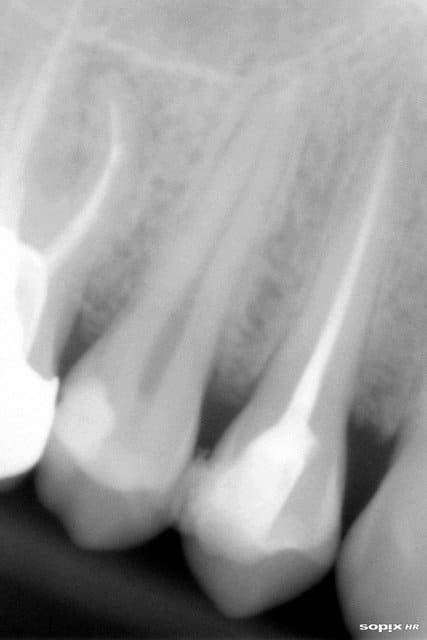

Bon, vu comme ça, ça a l'air de rien.

Mais si vous aviez vu l'ouverture buccale de ce gars, vous comprendriez pourquoi je suis content de cette endo de 38.

R13 jjkb0b - Eugenol

26/02/2013 à 18h26

Je me suis dit que le risque serait encore plus important avec une extraction.

Mais inutile de te dire que j'ai fait hyper gaffe à ne pas dépasser!